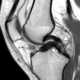

Absent bow-tie sign in knee meniscus